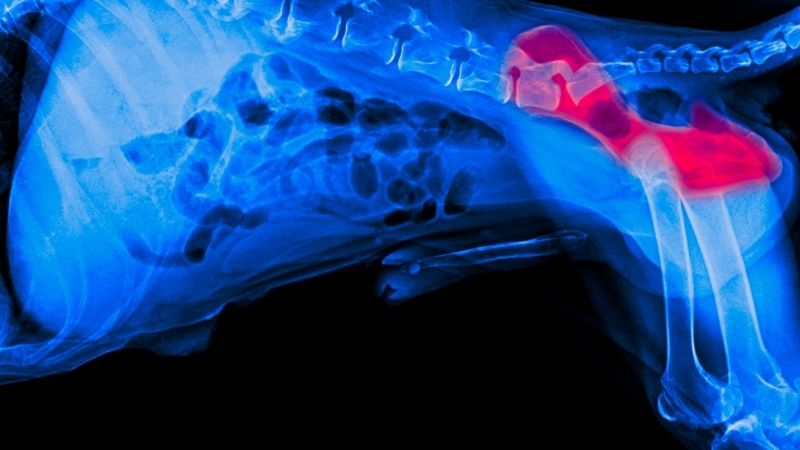

But to make a definitive diagnosis, it is necessary to take an X-ray of the dog, and for this, it is mandatory that the animal be anesthetized or deeply sedated so that the veterinarian can place it in the correct position and its muscles are totally relaxed.

To make a definitive diagnosis of hip dysplasia, it is necessary to take an X-ray of the dog, which must be anesthetized or deeply sedated.

And it is that, to take the X-ray, the dog must be in the frontal decubitus position, that is, lying on its back, with the front legs stretched towards the head and the rear legs fully extended symmetrically and turned inwards. Obviously, it is very difficult to get a dog to allow itself to be manipulated into this position and remain relaxed, which is why sedation is imperative.

Once the X-ray is done, the veterinarian will be able to know if your dog has hip dysplasia and, if it does, the degree and severity of it. The classification of the degree of hip dysplasia, according to the AVMA (American Veterinary Medical Association), is as follows:

• Grade A: Absence of radiographic signs of hip dysplasia

• Grade B: almost normal hip joints

• Grade C: Mild signs of hip dysplasia

• Grade D: Moderate signs of hip dysplasia

• Grade E: Severe signs of hip dysplasia